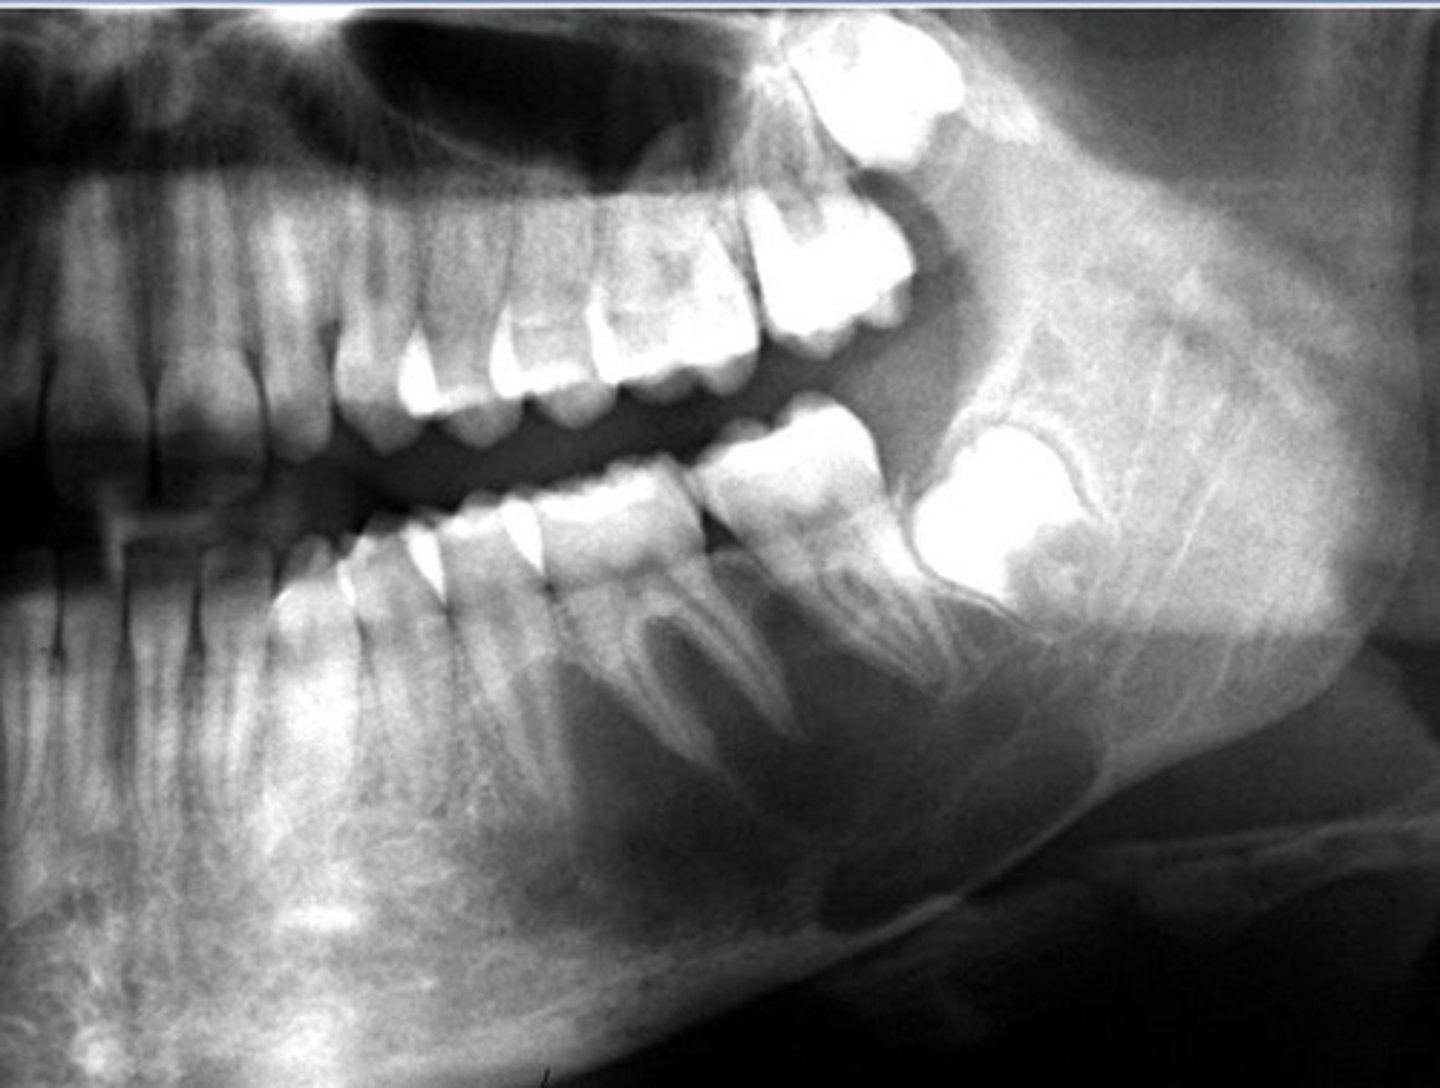

How would you describe the lesion?

- Periapical radiolucency associated with #30

- Has a band of sclerotic change extending from the apical radiolucency to the inferior alveolar canal and beyond

- Furcation involvement

(Furcation involvement as well as a band of sclerotic change extending from the apical radiolucency to the inferior alveolar canal and beyond)

What category would you put this lesion into?

Inflammation

what could be a differential diagnosis for this lesion? (select all that apply)

A. PCOD

B. multiple myeloma

C. apical rarefying osteitis

D. chronic sclerosing osteomyelitis

Also note apical rarefying osteitis #14 ( remnant root fragments, no crown due to caries)